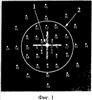

На фиг.1 изображено глазное дно пациентки Л. со светочувствительностью сетчатки до операции, где цифрами от 0 до 20 обозначена светочувствительность. Позицией 1 обозначен центр фовеа, позицией 2 – край фовеа.

Пример 1. Поясняется фиг.1-4. Пациентка Л., 64 лет. Диагноз: идиопатический макулярный разрыв III стадии. Корригированная острота зрения 0,2. При анализе данных микропериметрии в центре фовеа выявляется абсолютная скотома, светочувствительность 0 децибел, по краю фовеа светочувствительность в среднем 12 децибел, точка фиксации расположена на крае разрыва на расстоянии 290 мкм от фовеа. Проведена субтотальная витрэктомия. Через 1 месяц после операции отмечается субъективное улучшение, корригированная острота зрения 0,4. Закрытие разрыва подтверждается оптической когерентной томографией. При проведении микропериметрии в центре фовеа выявляется исчезновение абсолютной скотомы, светочувствительность 8 децибел, по краю фовеа светочувствительность 16 децибел, смещение точки фиксации на расстояние 150 мкм к центру фовеа. Эти данные позволяют сделать вывод о том, что хирургическое лечение является функционально эффективным.